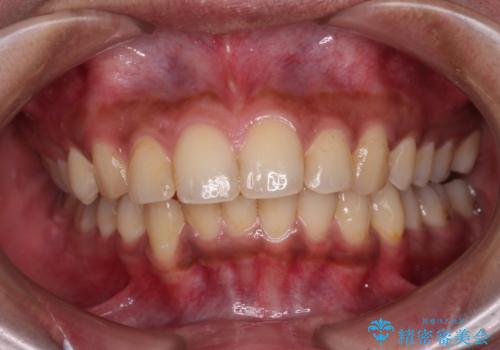

深い咬み合わせと前歯のデコボコ インビザラインによる矯正治療

- 前歯のデコボコと、食いしばりやすい咬み合わせを気にして来院された患者様です。

骨格的に下顎骨が左側に偏位しており、インビザラインでの矯正治療では奥歯の咬みにくさが残る仕上がりが懸念されましたが、新幹線での通院となるため、来院回数の少ないインビザラインでの治療を希望されました。

リスクをご説明した上で、インビザラインにより気になっている叢生と深い咬み合わせを改善していくこととしました。

治療途中では、左右ともに奥歯が咬みにくい状態が続き、問題なく噛めるようになるまでに長期間を要しました。

一方で、デコボコや下顎の前歯が隠れてしまうほどの深い咬み合わせはしっかりと改善されました。